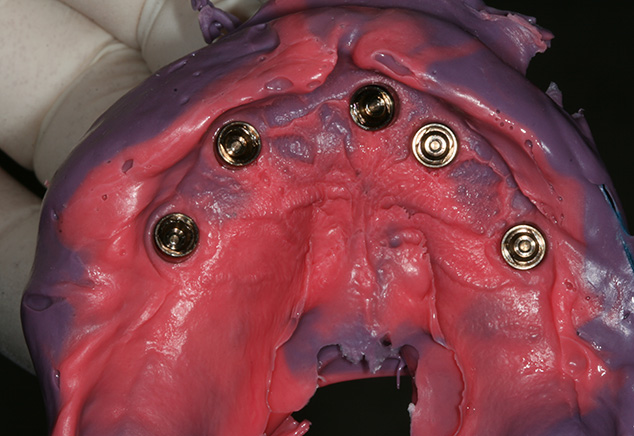

The patient was seen from Dr. Robert Levine's office for restorative records in preparation for immediate load protocol. The previously processed dentures were first checked with pressure paste to insure there was no contact of the intaglio surface with the tall healing caps. Bite registration material was then used to confirm there was no contact (Fig 9) and later will be used by the lab to articulate the models. Efforts were made to confirm the OVD (with the marked tongue depressor provided by Dr. Levine), incisal position, midline, plane of occlusion, and centric position with the prosthesis in place. Adjustments were made as needed. Photographs were acquired to document and relay information via e-mail to the lab technician. The lab will use the registration material left in the intaglio surface of the prostheses, as healing caps will be placed on the newly fabricated models. This allows the index to transfer the OVD and centric relationships with contact just on the healing caps. The soft tissue plays no role in this relationship. A bite registration was made to confirm centric relation. Healing caps were then removed and open tray impression copings were placed. If the connection between the implant abutments and the impression copings are not visualized, then x-ray confirmation of the connection is needed. Transfer Impressions were made using a custom tray and rigid impression material of choice, in this case polyether was used. Our lab courier delivered the dentures and impressions to the lab for the conversion to metal-reinforced, screw retained provisionals, which were delivered back to the restorative office within 24 hours.